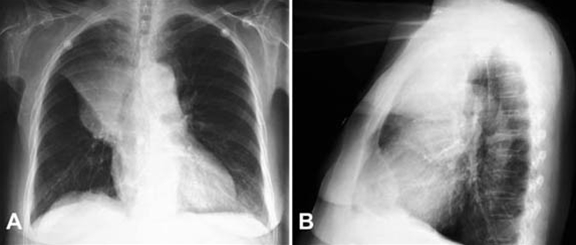

Lungekræft, front- og sidebillede

Frontal- og sidebillede af et bronkogent carcinom som har forårsaget atelektase af højre overlap.